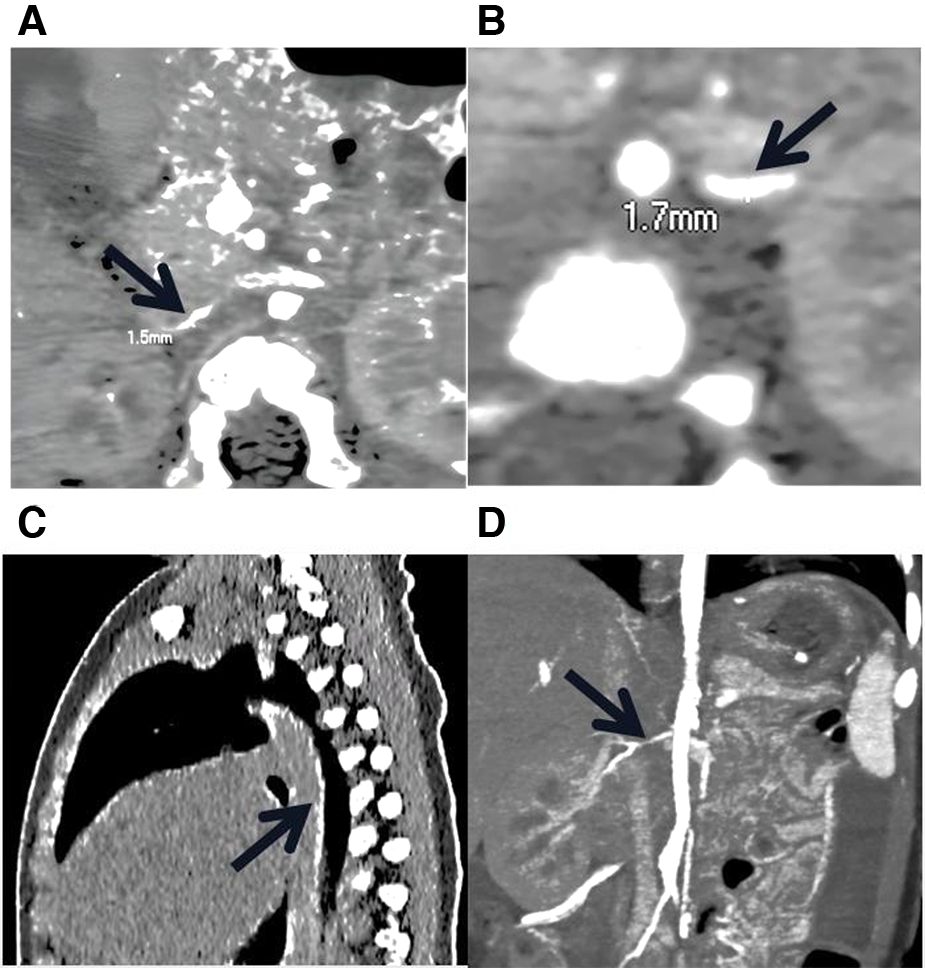

The proband was an 8-month-old boy admitted to our hospital for hypertension, hypertrophic cardiomyopathy (HCM), and heart failure. Physical examination revealed abnormal vital signs: a heart rate of 180 BPM, a respiratory rate of 46 breaths/min, and a blood pressure of 180/105 mmHg. An electrocardiogram showed sinus tachycardia and left ventricular hypertrophy. Laboratory examinations revealed hypophosphatemia (serum phosphate level of 0.94 mmol/L, normal range 1.5–2.3 mmol/L) and hypocalcemia (serum calcium level of 1.05 mmol/L, normal range 2.25–2.75 mmol/L). Other laboratory results for hereditary and metabolic disorders were negative. Echocardiography revealed hypertrophy of the ventricular wall, with a left ventricular ejection fraction of 62%. Doppler ultrasound revealed bilateral extensive calcification of the renal arteries. Enhanced CT further revealed extensive calcification of the iliac arteries, renal arteries, and abdominal aorta, without bone abnormalities (Figure 1).

Figure 1

Low-dose, enhanced CT of the child with GACI caused by a homozygous variation in ENPP1. (A) and (B) stenosis of bilateral iliac artery; the thinnest parts of the left and right iliac arteries are 1.7 mm and 1.3 mm wide, respectively. (C) The black arrow indicates the presence of calcification in the descending aorta, thoracic aorta, and abdominal aorta. (D) The black arrow indicates the stenotic right renal artery.